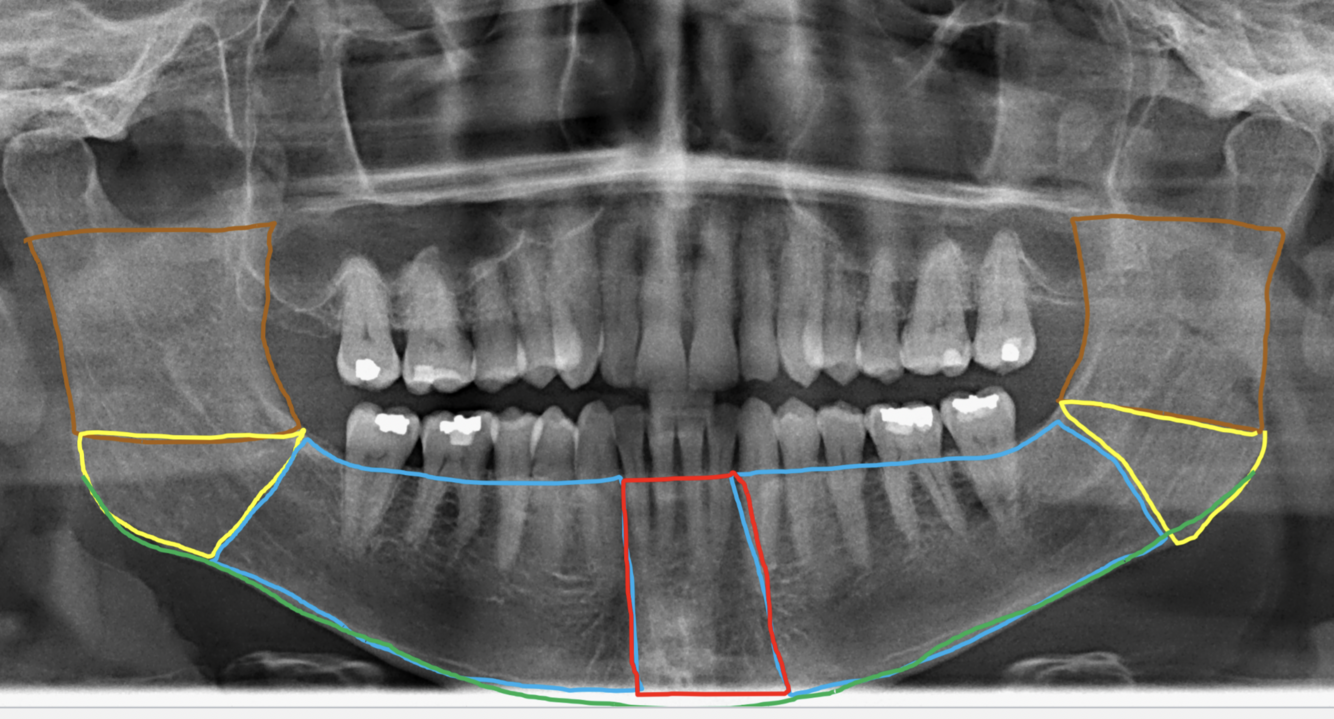

Label the following image:

1. blue: mandibular body

2. yellow: angle of mandible

3. orange: ramus of mandible

4. red: symphysis

5. green: inferior border